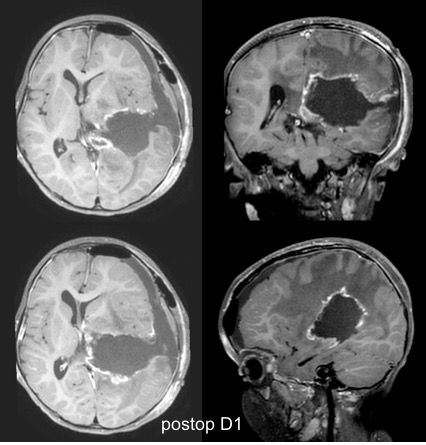

il commence avec la chirurgie en urgence, dans un but de décompression, de diagnostic histo-pathologique et si possible de résection totale, qui a un impact significatif sur la survie.

l’exérèse tumorale entraîne le plus souvent un saignement important, qui cesse avec la

fin de la résection. c’est donc une chirurgie lourde, surtout chez un petit nourrisson.